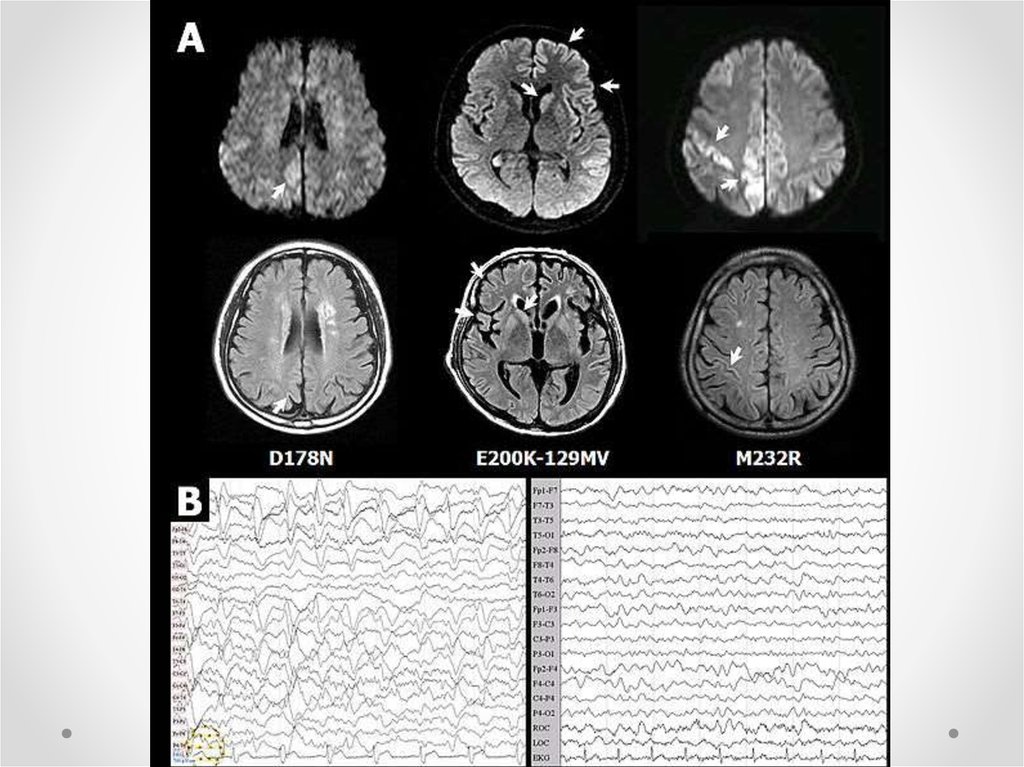

7. Клиническая картина

• Спорадическая БКЯ характеризуется

прогрессирующей

• Деменция

• Зрительные или мозжечковые нарушения

• Экстрапирамидная или пирамидная

дисфункция

• Миоклонус

• Акинетический мутизм на поздних стадиях